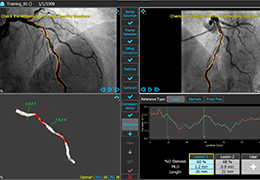

View X-Ray CT & MRI Scans Fast and Easily

Designed for surgeons, Pro Surgical 3D makes it easy to view patient scans quickly. Pro Surgical 3D facilitates the optimal 3D treatment and assessment workflows based on X-ray CT and MRI scans – and best of all, it’s FREE!

Traditional multi-planar slicing

High-quality and fast 3D reconstruction and 3D rendering

Multi-planar slicing.

Oblique slicing.